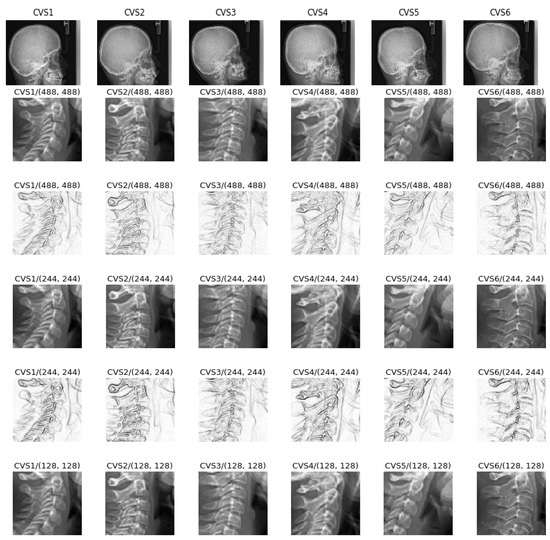

4.3. Comparison of a Simple Network on Different Preprocessed Images

- A cropping of images of the size 512 × 512 to the specific informative part of cervical vertebra and possibly resizing them to 256 × 256 for reducing the computational costs are enough. However, to improve more, we tried different pre-processing of the images: mean, median and entropic filter to the images.